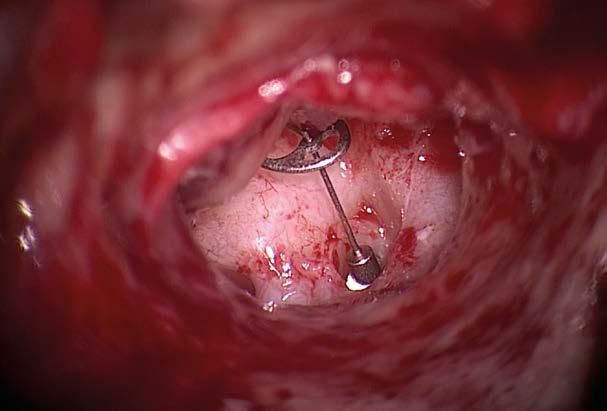

OMEGA CONNECTOR

OPTIMIZED FIT

In total ossicular reconstruction, movements of the tympanic membrane can alter the implant position on the stapes footplate. This risk may be reduced by using the OMEGA CONNECTOR together with a total prosthesis. The OMEGA CONNECTOR is designed to compensate for tympanic membrane movements and provide additional stability.

FLEXIBLE JOINT CONNECTION

With sufficient footplate access, the OMEGA CONNECTOR increases the medial surface contact of a total prosthesis. The micro ball joint connects with the cannulated stem of the KURZ total prosthesis. In this way it accommodates drum to head plate angles without prosthesis manipulations.

STABLE CONNECTION

An aspiration tip is ideally used to place the OMEGA CONNECTOR first into the middle ear. The cupped medial end of the total prosthesis is assembled with the OMEGA CONNECTOR in situ. A snug and stable fit between the two prostheses makes fixation with adhesive unnecessary. The undersurface of the shoe has a longitudinally milled recess to compensate for footplate irregularity.

QUICK DETERMINATION OF AVAILABLE SPACE

With the aid of the specially developed OMEGA CONNECTOR Sizer the surgeon can intraoperatively determine whether adequate space prevails for the OMEGA CONNECTOR between the stapes crura remnants. The measuring tip of the OMEGA CONNECTOR Sizer precisely corresponds to the dimensions of the OMEGA CONNECTOR.

Total Prosthesis

Stapes Footplate

Image courtesy of R. Mlynski, Rostock, Germany